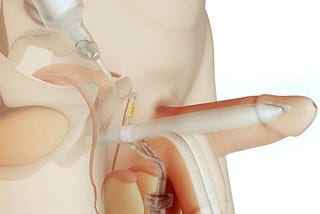

Penile Modification

Penile Modification 108 photos